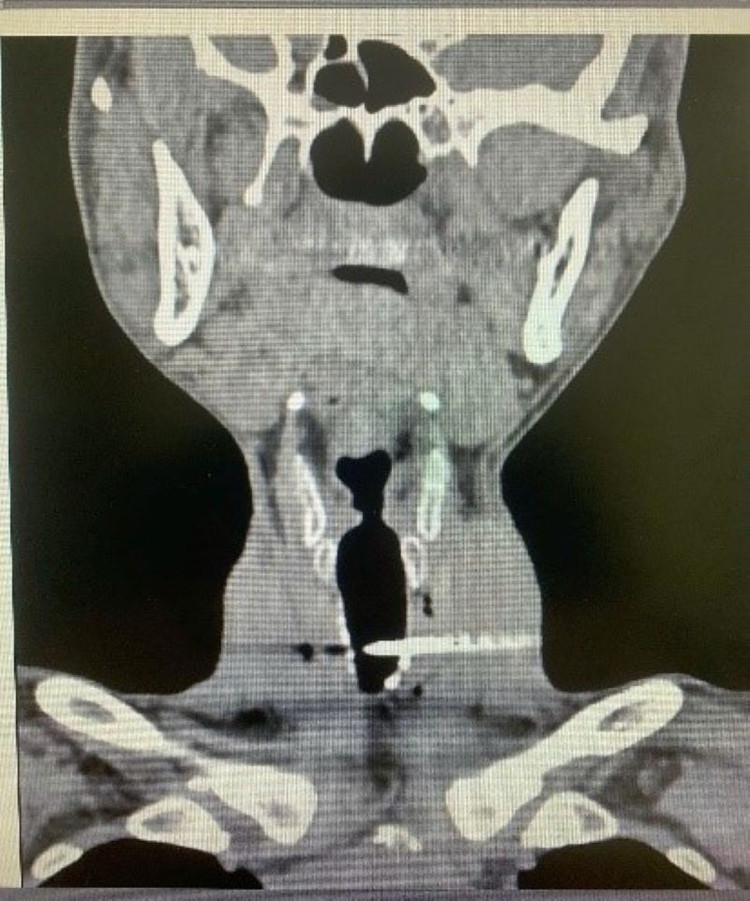

Ngày 3/8, bệnh nhân T.V.S (nam, 49 tuổi, trú tại tỉnh Bắc Ninh) được chuyển đến Khoa Cấp cứu – Bệnh viện Trung ương Quân đội 108 trong tình trạng nguy kịch: khó thở, vùng cổ trái có dị vật kim loại (đinh sắt) cắm sâu vào giữa cổ.

Theo lời kể của người nhà, khoảng hai giờ trước đó, trong lúc căng dây cước để thi công công trình, sợi dây bất ngờ bật ngược, khiến một chiếc đinh thép văng mạnh và đâm xuyên vào cổ bệnh nhân. Sau khi được sơ cứu ban đầu tại cơ sở y tế tuyến trước, bệnh nhân lập tức được chuyển đến Bệnh viện Trung ương Quân đội 108 để tiếp tục xử trí chuyên sâu.

Tại Khoa Cấp cứu, bệnh nhân lập tức được xử trí theo quy trình khẩn cấp: thở oxy, giảm đau, băng vết thương và chuyển chụp cắt lớp vi tính vùng cổ-ngực để đánh giá tổn thương.

Kết quả cho thấy dị vật xuyên qua thành bên trái khí quản và đường đi của tĩnh mạch cảnh trong trái, một tổn thương cực kỳ nguy hiểm, có nguy cơ gây suy hô hấp cấp, sốc mất máu và tử vong nếu không được can thiệp kịp thời.

Hình ảnh đinh sắt trên phim chụp - Ảnh BVCC